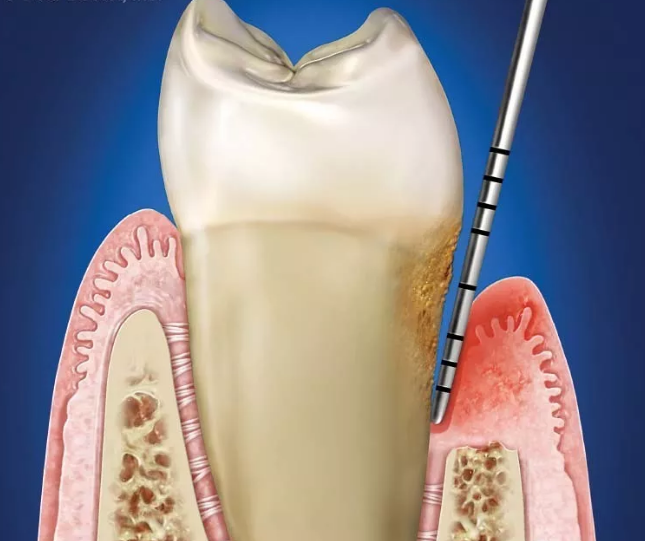

龈下刮治术则是指用比较精细的器械

把牙周袋内牙根上的牙结石刮除

换句话,龈下刮治也俗称“深度洁牙”

一般洁牙是清洁肉眼看见的牙齿表面

但一些牙结石位于牙龈下方

更深处的牙周袋内

龈下刮治就是清洁肉眼看不见的牙龈以下的结石

有了牙周袋之后,牙结石就顺着牙周袋

悄无声息地往下继续蚕食牙槽骨

步骤一、医生会对每一颗牙齿的牙周袋进行探查并记录 ,确定要进行刮治的牙齿。

步骤二、医生将微创的牙周器械伸入牙周袋内,清除牙面上的牙结石和菌斑,冲洗牙周袋,将残存的牙石碎片彻底清除,局部应用消炎药物。